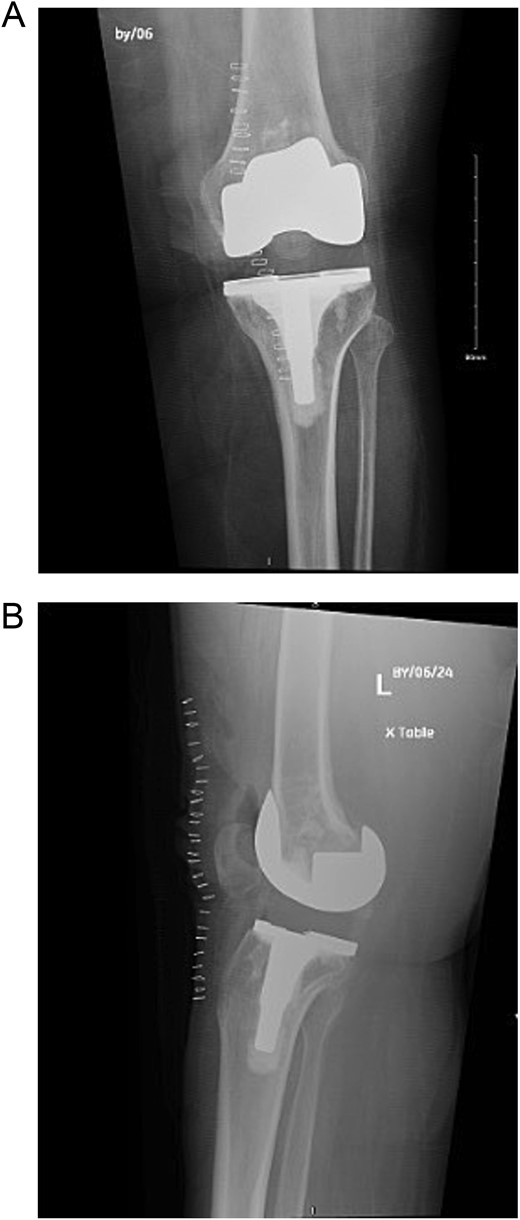

Upon examination in the emergency room, the patient was vitally stable, alert, and oriented. Her skin was intact, showing a healed wound. Mild swelling was noted over the left knee joint, with no erythema or ecchymosis. She had tenderness over the medial surface of the knee. The active ROM was from 0º to 90º and was limited due to pain; the passive ROM was from 0º to 110º with a clicking sound during flexion. Soft compartments were noted, and distal neurovascular examination was unremarkable (Fig. 2).

(A) Anteroposterior view of the left knee in the emergency department. (B) Lateral view of the left knee in the emergency department.